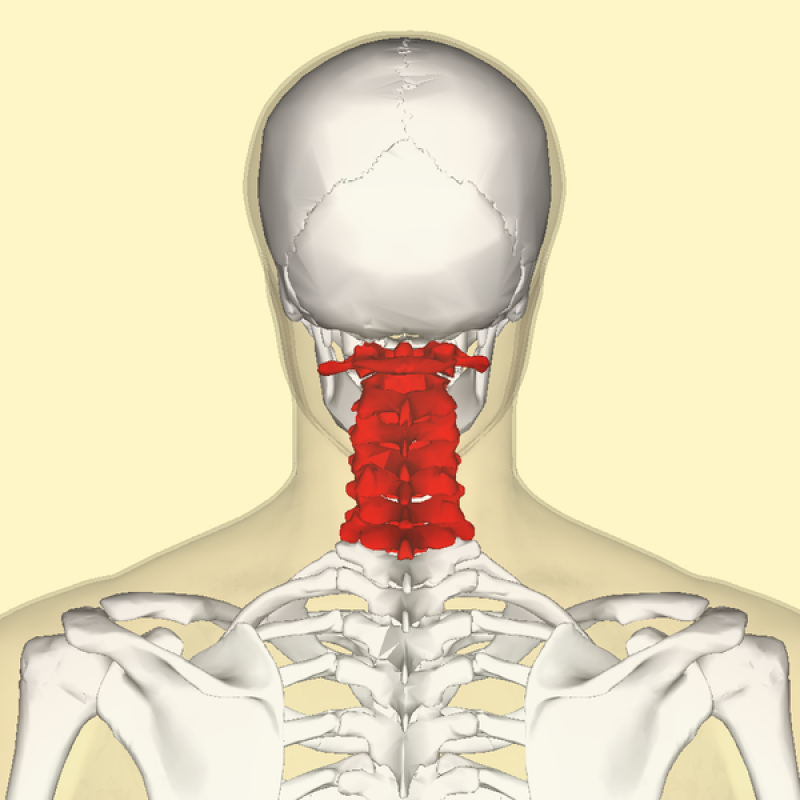

Exame de Imagem de Ressonância Magnética da Coluna Cervical

Exame de Imagem de Ressonância Magnética da Coluna Cervical

Exame de Imagem de Ressonância Magnética da Coluna Cervical

Medicom ExamesCom um exame de imagem é possível diagnosticar algum tipo de câncer e dessa forma seguir com um tratamento. Além do exame de imagem são feitos... Cotar Agora Saiba Mais